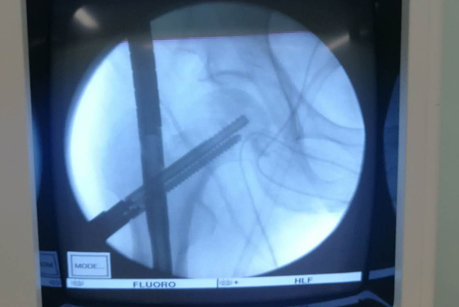

在手术之前,首先做股骨全长薄层扫描CT,将患者股骨影像及数据搜集并记录下来,通过3D打印技术制作出一个1:1比例的股骨“复制品”,它的直径、长短、髓腔形态都与患者真实情况完全相符,甚至患者骨骼上每一块凹陷与凸起,每一点纹理和痕迹都呈现得一清二楚。然后通过在体外对模型进行模拟手术操作,准确制订出了髓内钉的入针点、长度、直径,精确计划出远端锁钉准确位置。手术时,按着术前的设计顺利完成了手术,大大缩短了手术时间,减少了对患者的创伤。术后影像骨折解剖复位,锁钉位置精准无误,术后患者顺利康复。

术中影像